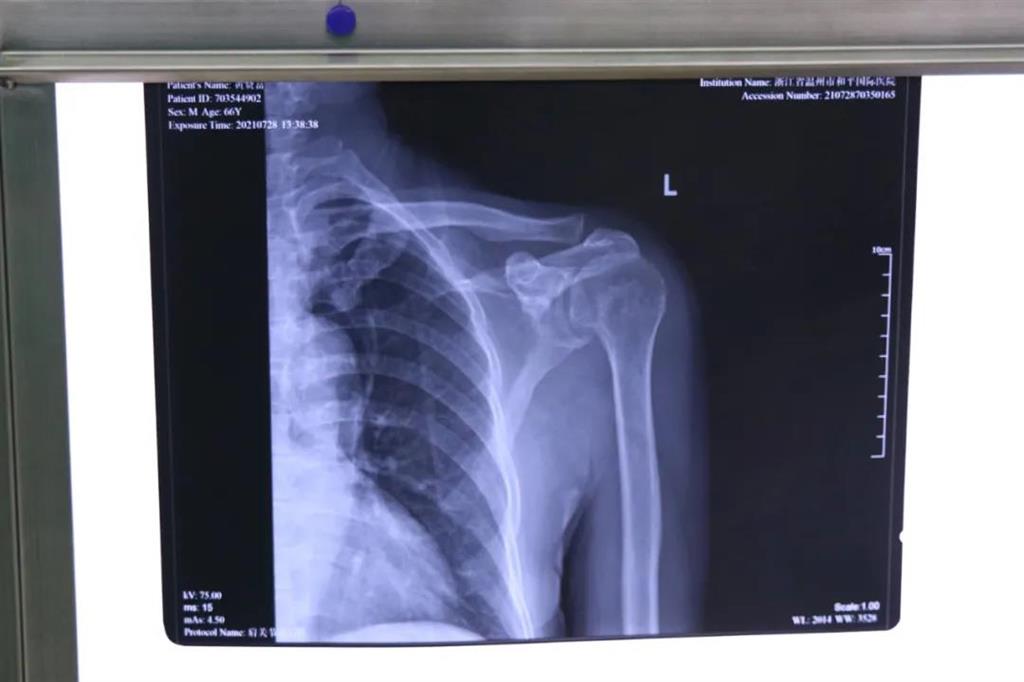

患者黃大叔(66歲)為"左肩袖損傷"病人,8年來(lái)左肩部持續(xù)疼痛伴肩關(guān)節(jié)活動(dòng)輕微受限。患者于近期左肩部疼痛加重,抬肩困難,難以完成穿衣服等日常生活活動(dòng)。

術(shù)前檢查見左肩關(guān)節(jié)輕度腫脹,左肩關(guān)節(jié)岡上肌附著處壓痛明顯,MRI提示左岡上肌肌腱斷裂回縮,岡下肌腱部分撕裂。為此和平國(guó)際醫(yī)院關(guān)節(jié)鏡微創(chuàng)團(tuán)隊(duì)為患者制定了詳細(xì)的一期、二期手術(shù)方案。此次手術(shù)為一期肩袖成形術(shù)